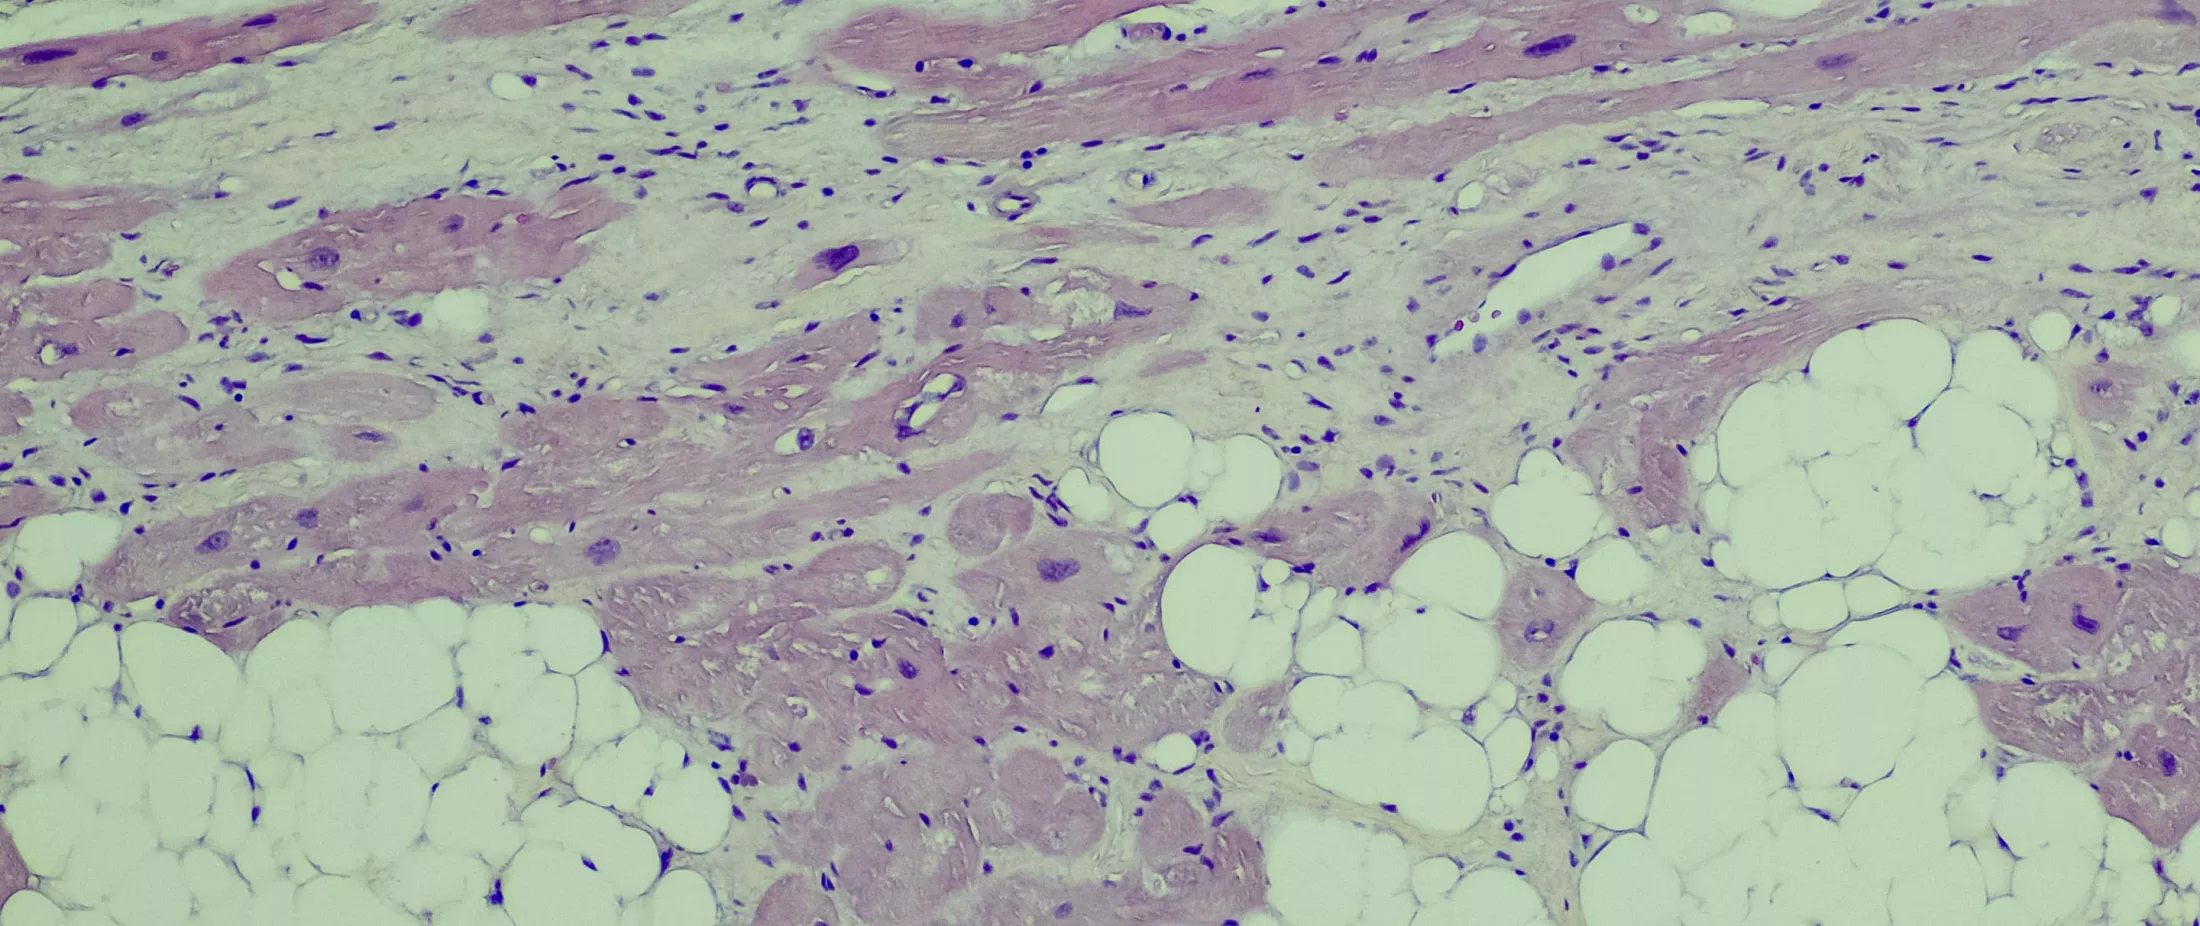

Inherited arrhythmia disorders are a group of rare genetic conditions that are associated with an abnormal heart rhythm and an increased risk of sudden cardiac death in young people. Inherited cardiomyopathy disorders, such as hypertrophic, restrictive and familial dilated cardiomyopathy, are a group of genetic diseases of the heart muscle that can lead to heart dysfunction and/or failure and represent another major cause of morbidity and mortality if undiagnosed and/or left untreated. A rare form of restrictive cardiomyopathy includes cardiac amyloidosis, which can result from a rare genetic type of amyloidosis and lead to an abnormal deposition of amyloid proteins in the heart tissue. It can cause slowly progressive cardiac disease in elderly individuals, but it can also be seen in young people and can result in stiffening of the heart muscle and heart failure.